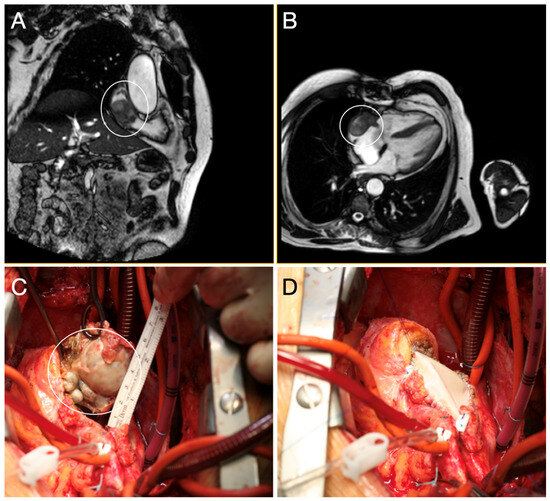

- Huang, J.; Lei, C.; Hsi, D.H.; Zheng, M.; Ma, H.; Ta, S.; Hu, R.; Han, C.; Li, W.; Li, J.; et al. Echocardiography-Guided Radiofrequency Ablation for Cardiac Tumors. JACC CardioOncol. 2024, 6, 560–571. [Google Scholar] [CrossRef] [PubMed] [PubMed Central]